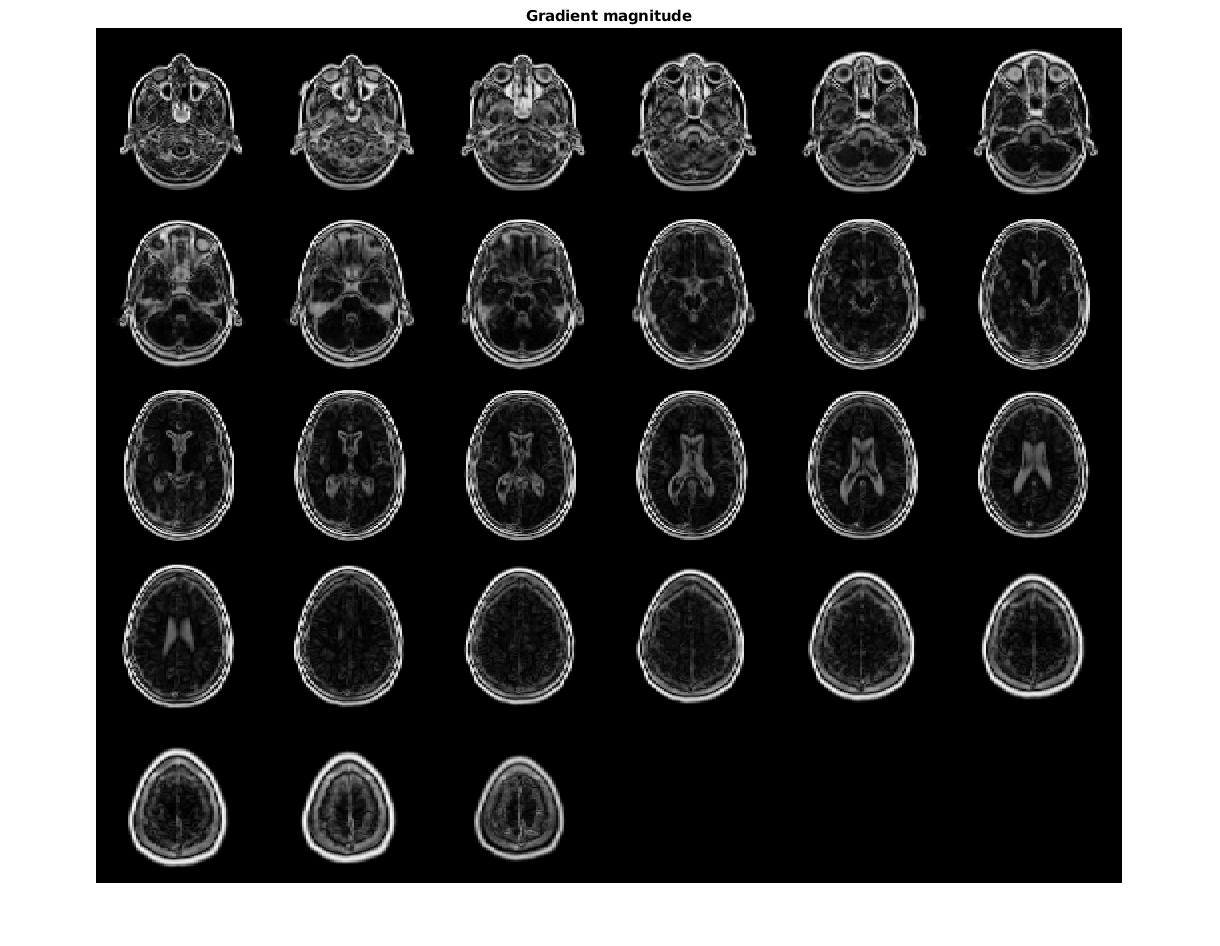

Считайте 3-D данные в рабочую область и подготовьте его к обработке.

volData = load('mri');

sz = volData.siz;

vol = squeeze(volData.D);

Вычислите градиенты.

[Gmag, Gaz, Gelev] = imgradient3(vol);

Визуализируйте величину градиента как монтаж.

figure,

montage(reshape(Gmag,sz(1),sz(2),1,sz(3)),'DisplayRange',[])

title('Gradient magnitude')

Figure contains an axes. The axes with title Gradient magnitude contains an object of type image.